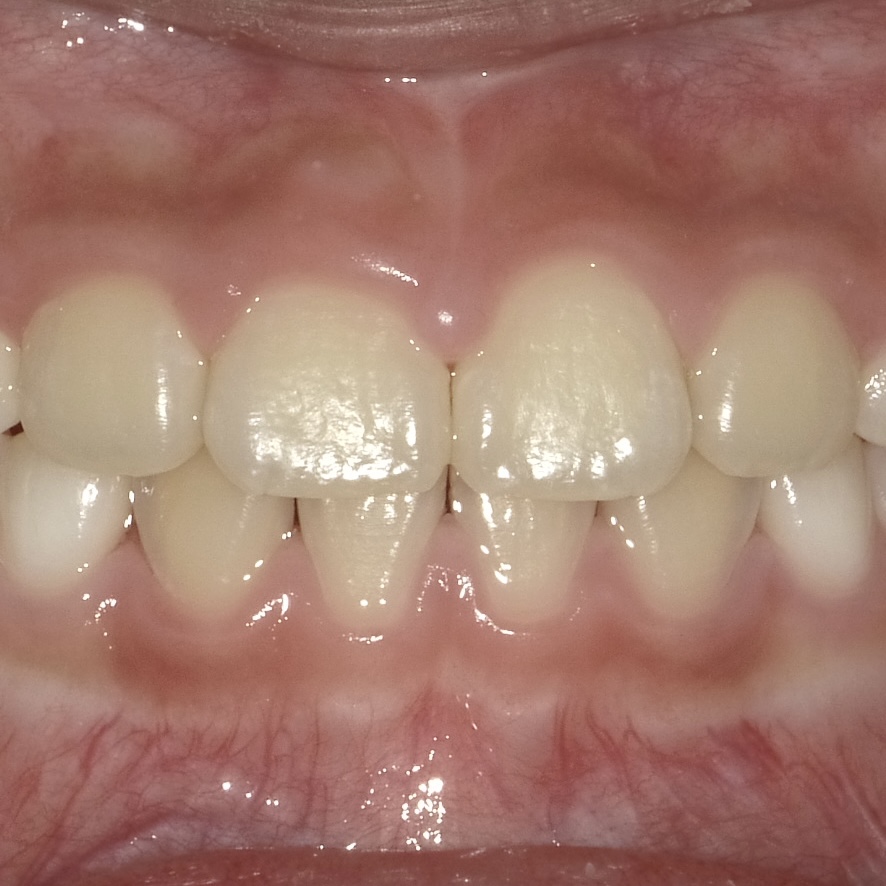

正中離解の矯正治療では、前歯の表側にマルチブラケット装置を装着して歯を動かします。

1番初めの写真から矯正治療が進んだ後の写真がこちらです。